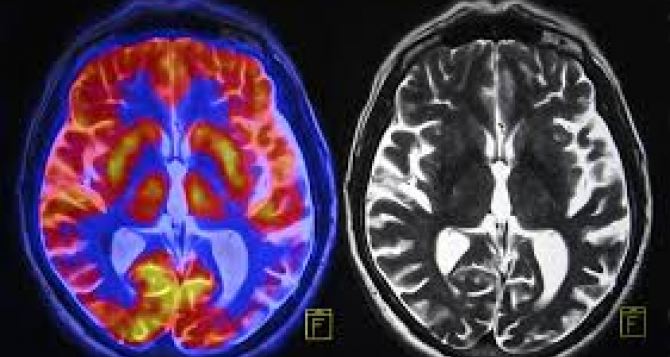

Международная команда ученых выяснила, что с возрастом мозг теряет способность эффективно производить важные белки, и это связано не с поломкой генов, а со сбоями на уровне синтеза — так называемым «застреванием» рибосом.

Обычно предполагается, что если уровень мРНК стабилен, то и соответствующий белок должен вырабатываться в том же объеме. Однако эксперимент показал «рассогласование»: мРНК оставалась на прежнем уровне, а количество белка уменьшалось. Особенно это касалось белков, богатых основными аминокислотами.

Причина в том, что рибосомы чаще «застревали» при переводе таких участков кода. Это приводило не только к падению синтеза, но и к накоплению неправильно свернутых белков и воспалительному ответу — признакам, характерным для болезней Альцгеймера и Паркинсона. С возрастом в мозге рыбок снижалось общее число полноценных рибосом. Неожиданно это помогало некоторым процессам: например, улучшался синтез белков митохондрий, поскольку при избыточном количестве рибосом такие мРНК наоборот работали менее эффективно.

Эксперимент с частичной блокировкой протеасомы — системы утилизации белков — показал: потеря нужных белков не связана только с их разрушением. Главная проблема именно в нарушении перевода мРНК в белки. Авторы предполагают, что рибосомное «застревание» может быть универсальным механизмом старения мозга, объединяющим несколько ключевых последствий — геномную нестабильность, снижение биосинтеза и воспаление.

Если удастся найти способы облегчить работу рибосом или повысить эффективность трансляции, это может стать новым направлением терапии возрастных заболеваний мозга. Следующий шаг ученых— изучение образцов человеческого мозга и проверка того, можно ли восстановить контроль над трансляцией для замедления возрастных изменений.